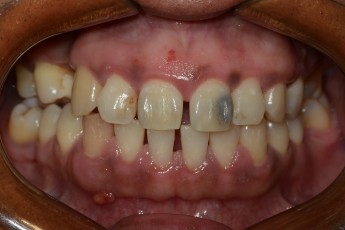

BEFORE & AFTER